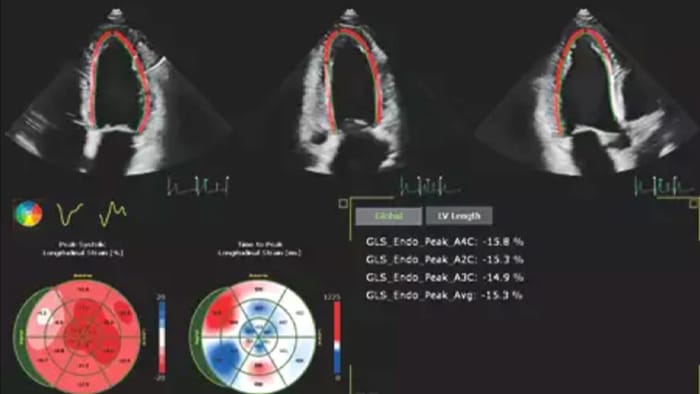

Robust and reproducible imaging tools are important to diagnose and monitor disease progression in heart failure. Current guidelines support the use of advanced echocardiography tools such as longitudinal strain and 3D assessment of LV and RV volumes and function.

Image showing results of automation for robust, proven reproducible cardiac quantification in both 2D and 3D

Automation for robust, proven reproducible cardiac quantification in both 2D and 3D.